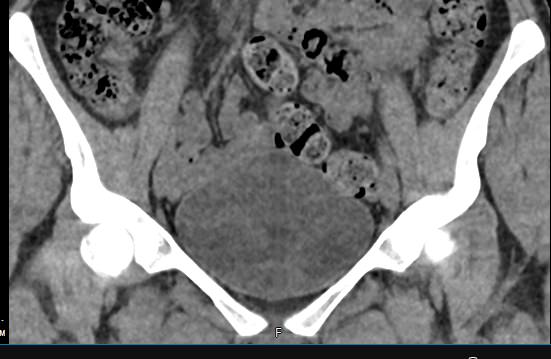

Мультиспиральная КТ мочевого пузыря является частью протокола обследования органов малого таза. Это высокоинформативный рентгенологический метод исследования, позволяющий детально визуализировать мочевой пузырь, нижнюю часть мочеточников, внутренние половые органы, прямую кишку.

Зачастую подобное исследование проводится при мочекаменной болезни (МКБ) для выявления конкрементов, определения их положения, размеров и плотности. Локализация конкремента существенно влияет на терапевтическое лечение МКБ, а наличие дивертикулов стенки мочевого пузыря на возможность самостоятельного выхода камня.

Также при данном исследовании возможно выявить утолщение стенки мочевого пузыря, что при диффузных изменениях может соответствовать проявлениям цистита, а локальные или неравномерные утолщения – характеризовать патологический процесс обусловленный новообразованиями.

Что позволяет увидеть КТ мочевого пузыря

- цистит;

- дивертикулы мочевого пузыря

- цистоцеле

- уретероцеле

- варианты строения мочеточников

- камни мочевого пузыря;

- травмы, разрывы и растяжения органа;

- опухолевые новообразования.